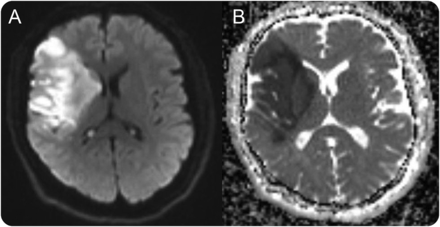

一名56岁男子提出后右大脑中动脉梗塞(图)。除了左轻偏瘫和忽视,他无法接近他的左眼命令(视频首页Neurology.org),尽管他能够自发地眨眼,保持闭着眼睛在睡觉。他可以保持关闭双眼一次手动关闭。失用症的眼睑闭合眼睑闭合贬值带来的是杰出的临床能力眨眼反射性和保持眼睑闭包。动眼神经的皮质的激活与自愿眼睑闭合和有关在右额叶和顶叶病变眼睑闭合失用症。1,2